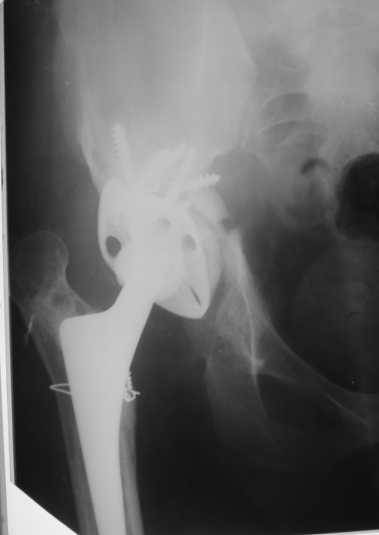

2003 г. нестабильность тазового компонента (рис. 2) - протез удален.

2005 г. при падении с высоты - перелом бедра в верхней трети, наложение АВФ . 3 года пациент ходил с аппаратом(рис. 3).